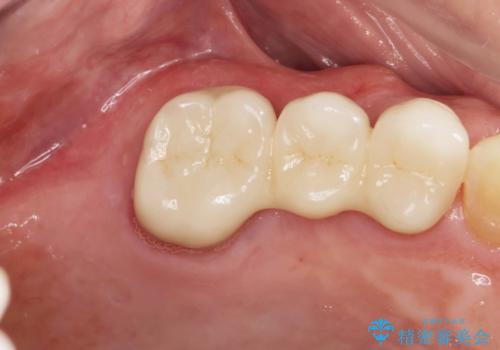

審美的かつ、噛みやすい仕上がりに満足いただくことができました。

今後最後方臼歯がないためブリッジに対する力が過大とならないよう噛み合わせの変化を注視する必要があります。